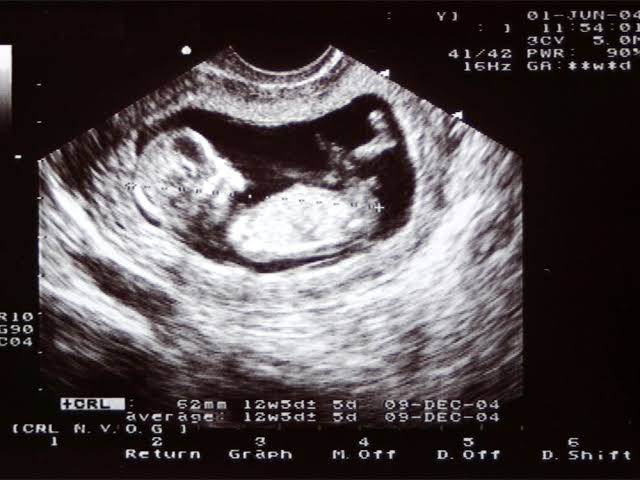

İlişkinin üstünden 2 ay geçmiştir son adet tarihinize göre gebelik hesaplanıyor yani o mantıkla 3 aylık hamile olmanız lazım. 3 aylık hamilelik büyük bi mürdüm eriği kadar, kolu bacağı belirgin bi canlı formunda. Var mı öyle bi şey şu attığınız ultrasonda?ya kusura bakmayın sizlere de habire soru soruyorum ama ben bugün kasıklarımın agrısı cok oluyor regl de hala olamadım diye tekrardan gittim ultrasonda polikist dendi ve iltihap varmış doktor o şekilde söyledi ama burada daha öncelerinde bir yazı okumuştum birisinin doktoru polikist demis ama megersem hamileymiş görememiş öyle bir şey olma ihtimali yoktur değil mi sonuçta kanımda da çıkmadı üstüne 2 ay olacak az kaldı?? Ultrasonumu da atıyorum burda bile muhtemelen stresten bir şey görüyormuş gibi hissediyorum aydınlatırsanız sevinirim

ya kusura bakmayın dediğim gibi şu sağ tarafta sanki öyle görür gibi hissettim atmak istedimİlişkinin üstünden 2 ay geçmiştir son adet tarihinize göre gebelik hesaplanıyor yani o mantıkla 3 aylık hamile olmanız lazım. 3 aylık hamilelik büyük bi mürdüm eriği kadar, kolu bacağı belirgin bi canlı formunda. Var mı öyle bi şey şu attığınız ultrasonda?

Buyrun 3 aylık ultrason. Nerde gördünüz bunu işaretleyin görelim biz de :))